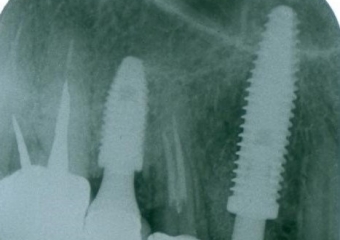

Rx Periapical controle 1 mes 21-11-16 - Clínica Cliniface

Rx Periapical controle 1 mes 21-11-16